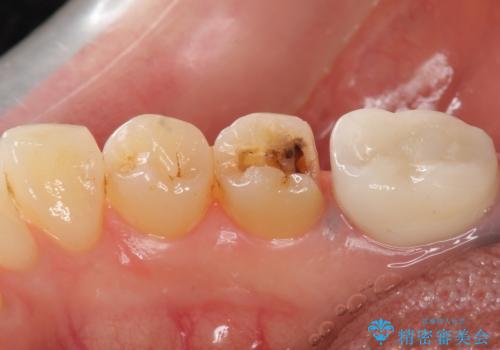

- 銀歯がしみることを主訴に来院されました。

銀のつめものを除去したところ、大きなう蝕を認めました。

咬合力が強いため、割れる心配がなく強度の高いPGA(ゴールド)インレーをご希望されました。